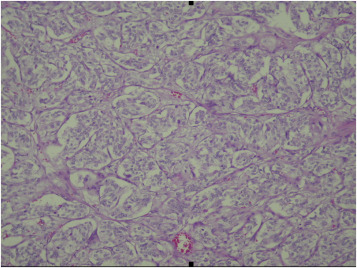

Tumor was composed of polygonal cells arranged in characteristic nested pattern ...

Tumor was composed of polygonal cells arranged in characteristic nested pattern “Zellballen.” Cytoplasm was amphophilic to basophilic.